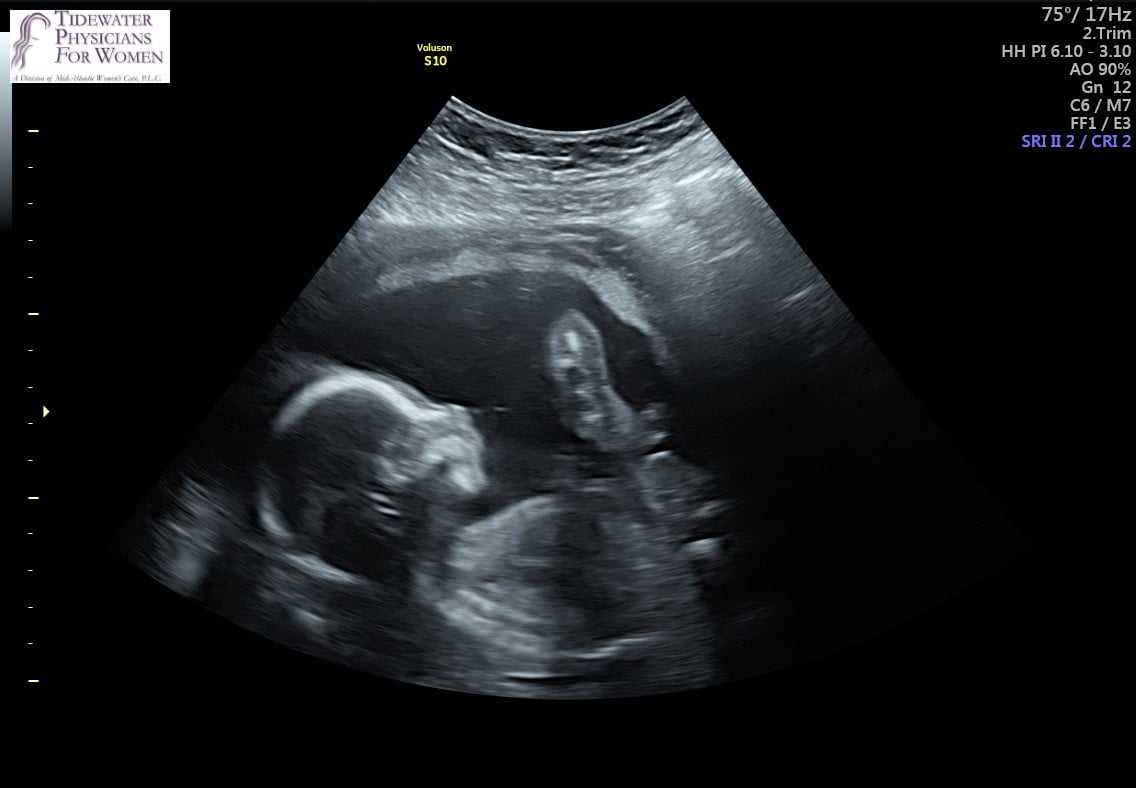

Had my dating US on Wednesday. Baby was measuring ahead a few days, so that puts me at 11wks today, if i understood correctly. Placenta appeared to be developing anteriorly.

NT scan was normal, heart was 146 BPM. Saw 2 arms, 2 legs, 2 eye sockets, and the brain. Will find out NIPT results and sex by end of next week, hopefully!